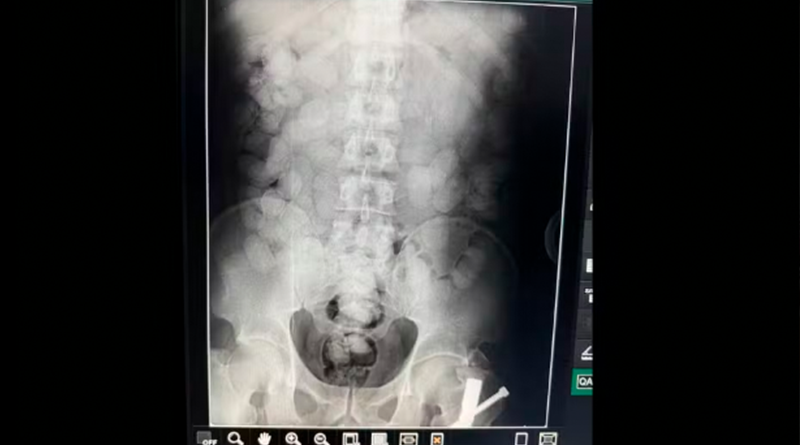

Suspeito confessou o plano de traficar as drogas para a Europa. Ele passou por raio-X no Hospital Metropolitano de Belém. — Foto: Ascom/PF

Segundo a PF, o abordado confessou a intenção de tráfico internacional de drogas, passou por raio-X no Hospital Metropolitano de Belém e agora aguarda, sob acompanhamento médico, que a droga seja expelida.